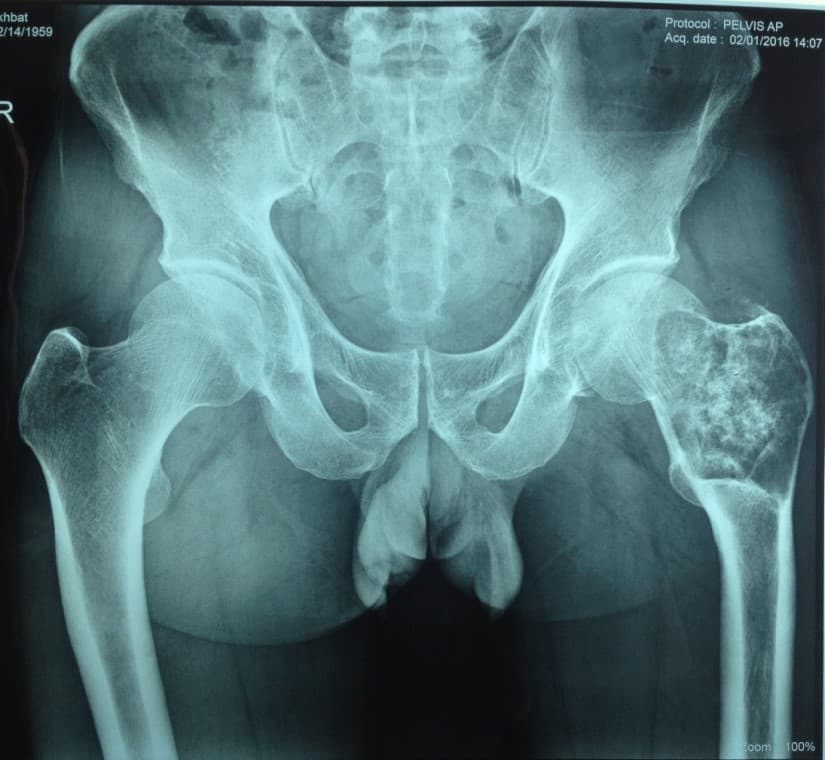

Мэс заслын өмнөх онош: Зүүн дунд чөмөгний түнхний үе орчмын ясны хавдар

Хийгдсэн мэс заслын нэр: Дунд чөмөг-түнхний хавдрын хиймэл үе суулгах мэс засал. Эмнэлэгт хэвтсэн ор хоног 10.

Зураг1. Зүүн дунд чөмөгний түнхний үе орчмын ясны хавдар

Зураг 4. Мэс заслын дараах рентген зураг

Өвчтөний ерөнхий биеийн байдал хурдан сайжирч, шарх эдгэрсэн, хүндрэл тохиолдоогүй.